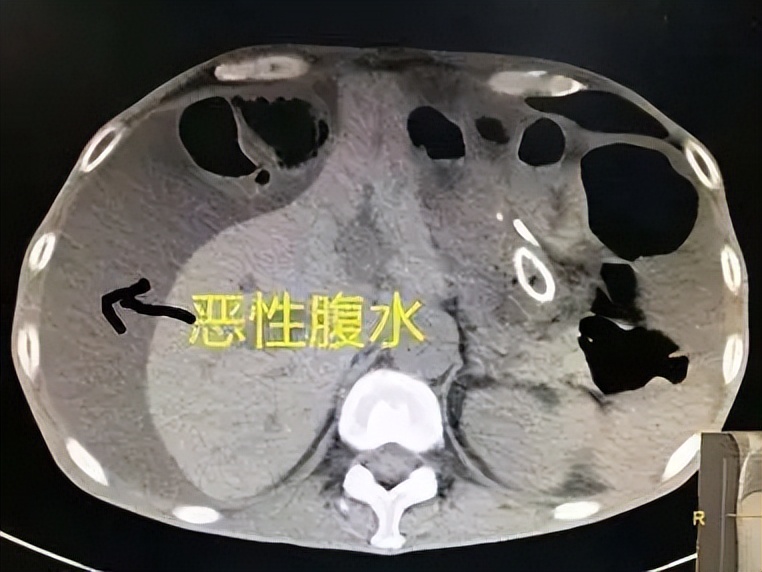

腹水是晚期恶性肿瘤的代表性症状之一,腹水一旦发生会直接影响肿瘤患者的生活质量和生存期,所以肿瘤患者对于腹水两个字是有畏惧心理的。

我在临床当中常用扶正祛邪、利水祛湿、清热解毒的方法治疗。给大家分享一个案例,这患者是肝癌腹水,在确诊肝癌前就已经有肝硬化了,病情比较严重,出现大量腹水,抽水大概抽出1升左右的积液,当时患者饮食欠佳、腹胀、憋闷身体虚弱不堪,没有办法承受多次的抽水,所以求助中医。